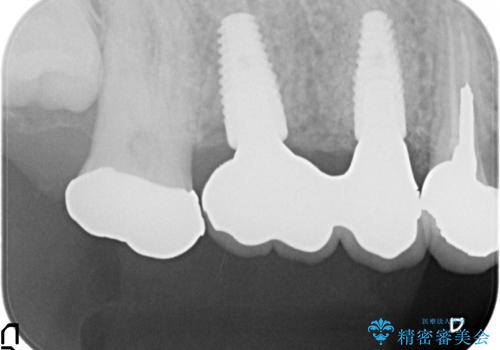

右上の567ブリッジを外したところ、右上5は歯根破折により保存不可能だったため、右上56部にインプラントを埋入し欠損補綴を行いました。

また右上5部に関しては抜歯時に歯槽堤保存術(抜歯窩に人工骨の填入を行う手術)を行い、骨の欠損を最小限に止めています。

- オールセラミッククラウン…¥100,000×2、仮歯…¥10,000×2、歯槽堤保存術…¥100,000、インプラント(ストローマン)…¥200,000×2、カスタムアバット…¥100,000×2費用は治療当時の料金となります

ストローマン(インプラント)について

当院では主にストローマンという種類のインプラントを治療に用いています。

ストローマンは世界的にもNo1のシェアを誇り、骨との適合にも優れたインプラントです。

カスタムアバットメントについて

カスタムアバットメントは患者様それぞれの歯茎に合わせて製作されたオーダーメイドのアバットメントです。

既製のアバットメントに比べ適合がよく、高い清掃性を誇ります。